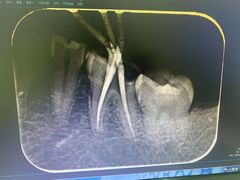

• 爱贝口腔·牙周诊疗·种植修复中心

• -爱贝口腔·牙周诊疗·种植修复中心

临空soho | 22-08-11